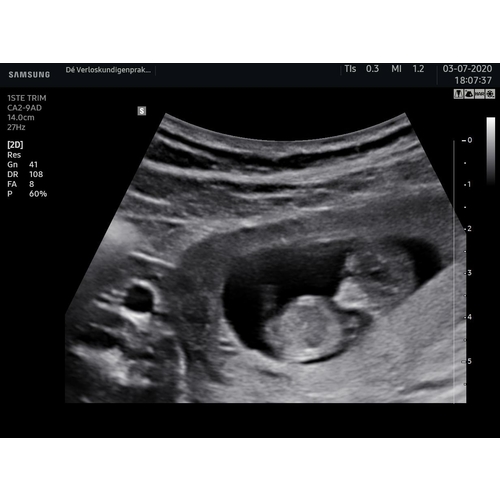

Voor 3D is het vruchtje dan ook nog te klein... Het is amper een paar centimeter groot én in volle ontwikkeling. Helemaal niks raar aan de hoofdvorm, en allesbehalve een reden om je zorgen over te maken.